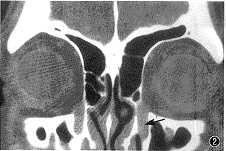

图1 左侧鼻丘为3气房,右侧鼻丘为2气房

鼻丘气房有单气房、 双气房及三气房等形态(图1)。以单气房为最多,为116侧(58%);双气房为62侧(31%);三气房为20侧(10%);无气房2侧(1%)。两侧鼻丘气房数比分别为:1∶1为38例(38%),1∶0为2例,1∶2为26例,1∶3为12例,2∶2为14例,2∶3为8例。100例中鼻丘发育者198侧(占99%),未发育者2侧(占1%)。